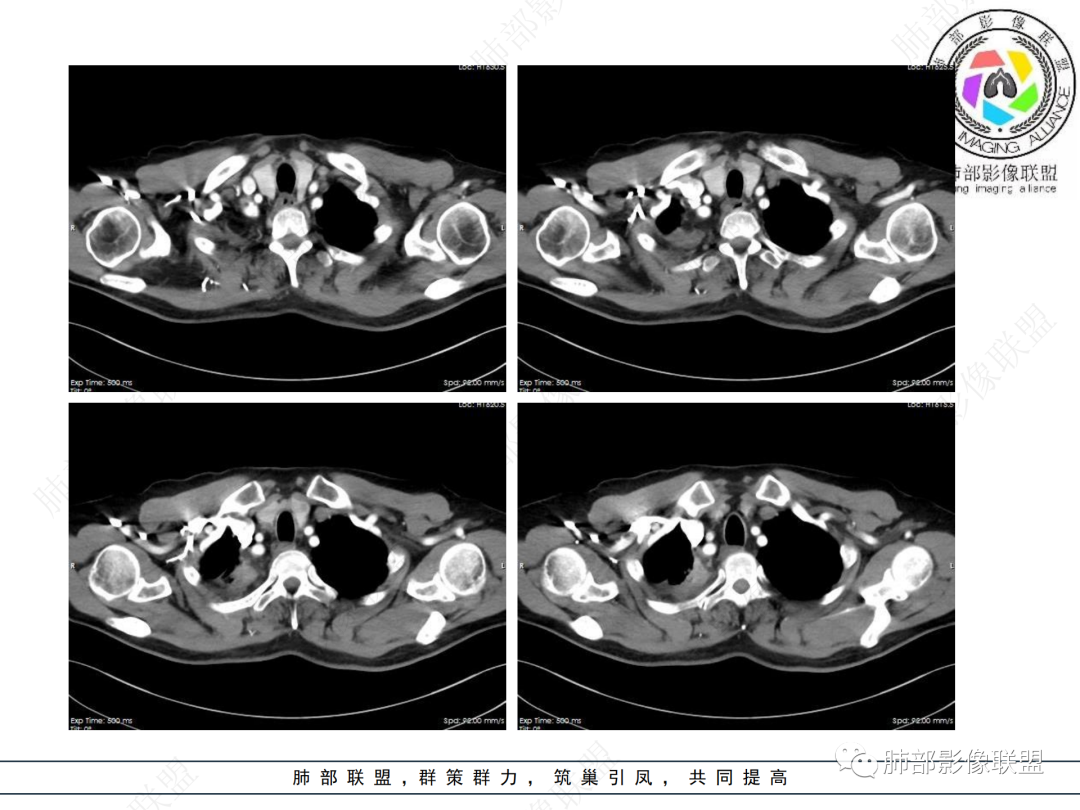

右肺上叶尖后段不规则斑块病灶,后缘以斜裂为界,有边缘平直,周围见纤维及多发小卫星灶,邻近胸膜反应性增厚,纵隔胸膜下少量积液,同时右肺中叶内侧段支气管扭曲及牵引性扩张,周边见爬行征,胸廊入口变窄,纵隔未见淋巴结肿大,综合上述慢性炎性肉芽肿,结核可能性大,支气管镜肺泡灌洗!

右上胸廓较对侧慢性缩小

右上叶体积缩小

慢性病变有

结合本病例,老年男性患者,慢性病程,急性加重,无吸烟史,影像学表现为右肺上叶尖后段斑片实变密度影,整体边界清晰,边缘平直收缩为主,周边散在纤维条索影,内部见支气管内粘液栓,血管影走形正常,没有明显破坏,增强扫描明显强化,缺乏典型分叶毛刺、胸膜改变,病灶也未显示清楚的磨玻璃勾边,病灶大而肺门纵隔未见肿大淋巴结,综合考虑慢性炎性肉芽肿可能性大。但恶性,结核能完全排除吗?我想对临床医生来说还是有很大考验的。